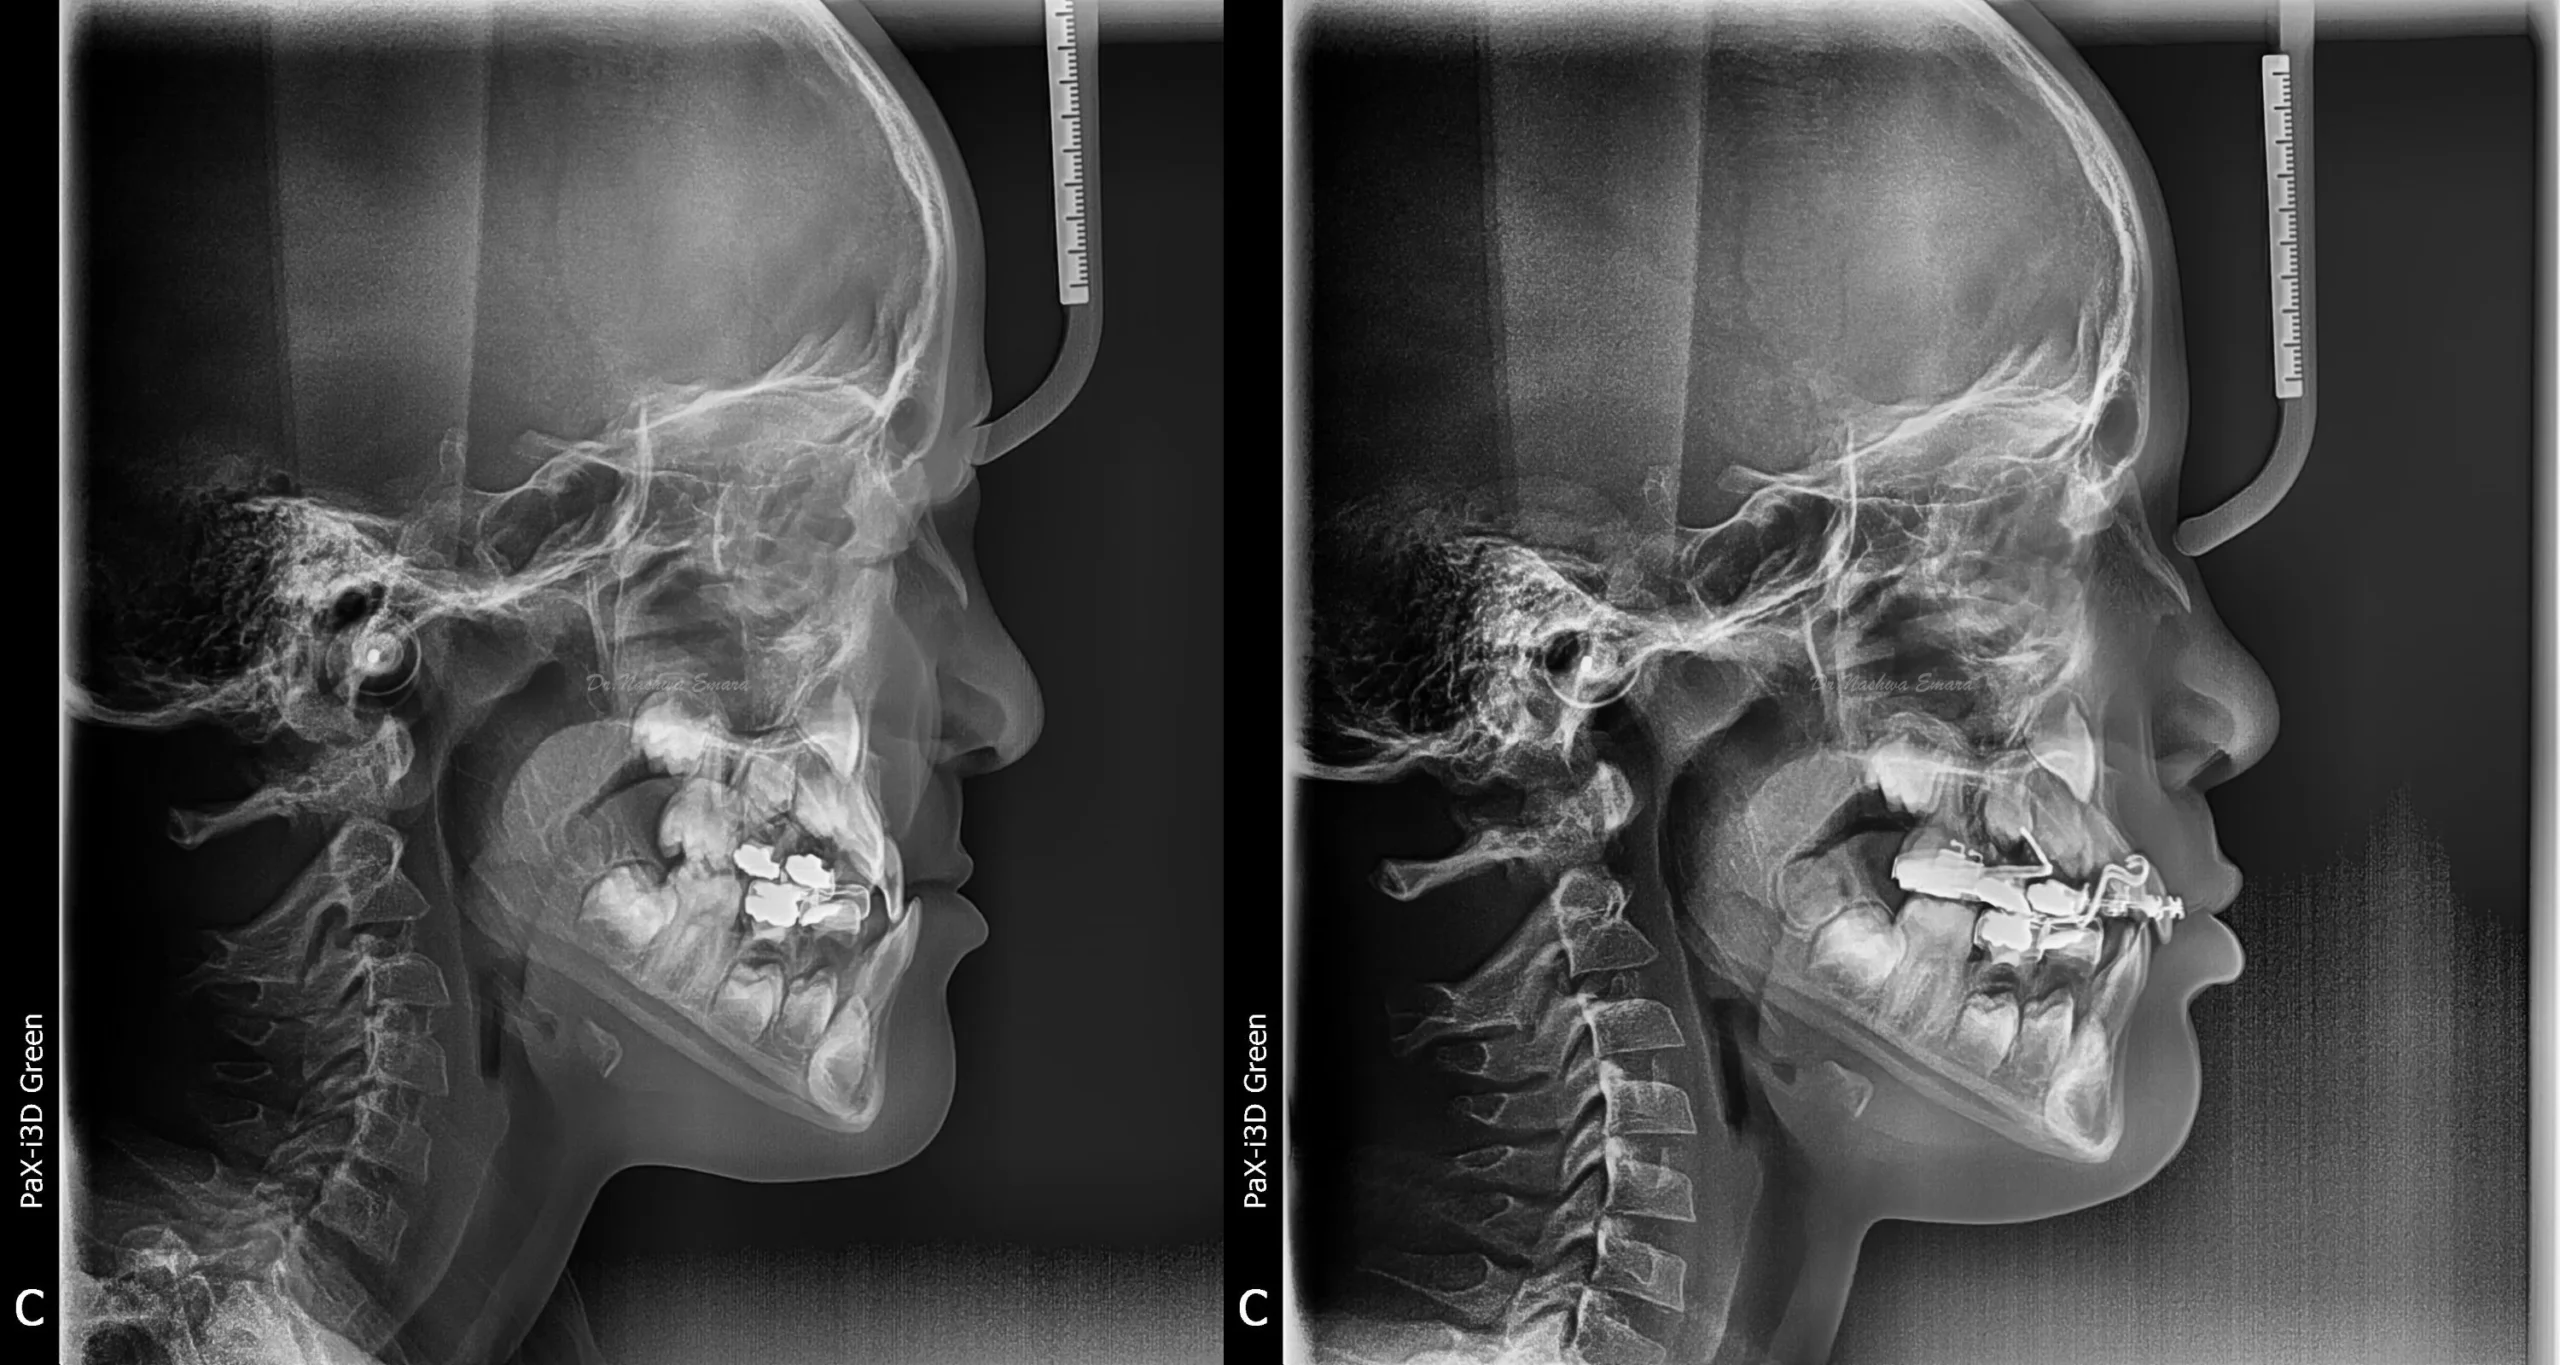

Orthodontics